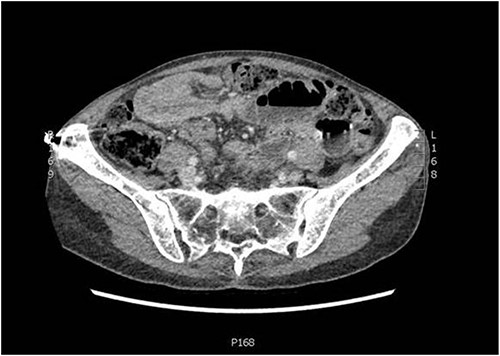

An independent 75-year-old woman presented to the emergency department with a 1-day history of crampy abdominal pain, nausea, vomiting and constipation. Her medical history includes multiple myeloma, which has been in remission for 4 years. She has no surgical history. On examination, she was alert but distressed with the pain. She was afebrile, normotensive and saturating well on room air with a regular pulse of 110, suggesting sinus tachycardia. Abdominal examination demonstrated a distended abdomen with tenderness around the umbilicus. There were no obvious hernias, and the rest of the abdominal exam was unremarkable. Her haematological investigations were unremarkable, and she had a lactate of 0.9 mmol/L. A computed tomography (CT) of her abdomen and pelvis with intravenous contrast was performed to investigate the cause of her pain. It demonstrated a partial or intermittent mid small bowel obstruction secondary to an intussusception (Figs 1 and 2).

Coronal slice of CT abdomen and pelvis showing an intussusception.